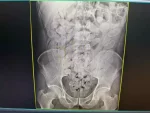

Grupo formado por oito bolivianos, sendo uma mulher e sete homens, foi flagrado transportando 645 cápsular de cocaína no estômago durante fiscalização da Receita Federal no posto Esdras, em Corumbá.  A ação fez parte da operação “Fronteira RFB”, realizada na quarta-feira (29/10), em parceria com a PM (Polícia Militar). Os agentes abordaram um ônibus de […]

(Bolivianos são flagrados com 645 cápsulas de cocaína no estômago)